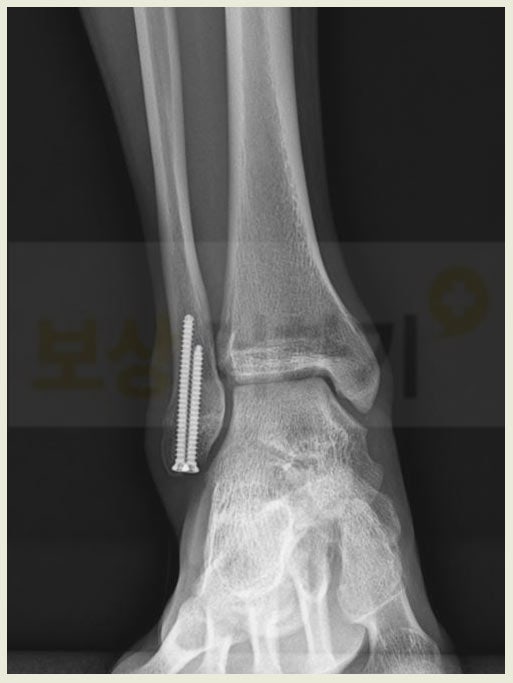

의뢰인은 외출을 하다가 계단에서 미끄러지셨습니다. 그 결과 복사 골절이 되셨어요. 복사뼈는 흔히 복숭아뼈라고 불리죠. 일상생활에서 발을 헛디디거나 발목이 접질리면서 흔하게 골절이 발생하는 부위입니다.

의뢰인의 경우 자연적인 유합이 어려워 수술을 시행받았습니다. 뼈를 제 위치로 맞춘 다음 나사못으로 단단히 고정을 시키는 내고정술이었습니다.